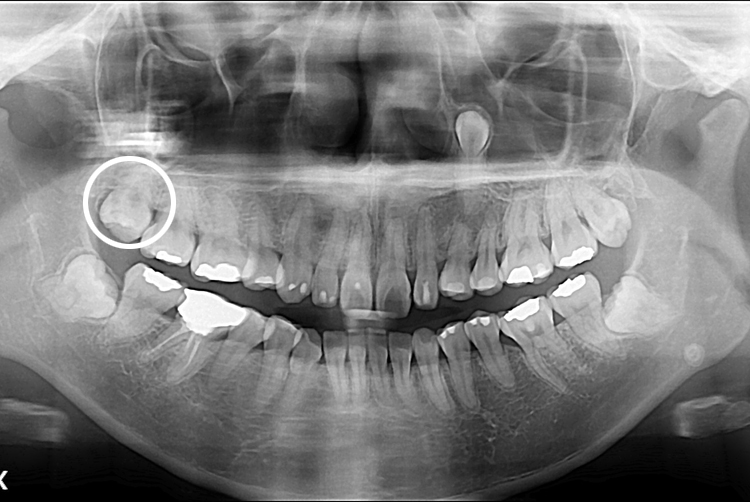

[사랑니] 매복 사랑니 발치

치료후 : 2019-06-25